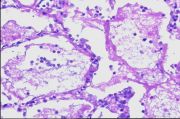

| 2021年12月10日 (五) 13:22 | 24号切片-小叶性肺炎-镜下观1.jpg (文件) |  |

145 KB | Cirno.9 | 基于MsUpload的文件上传 | 1 |